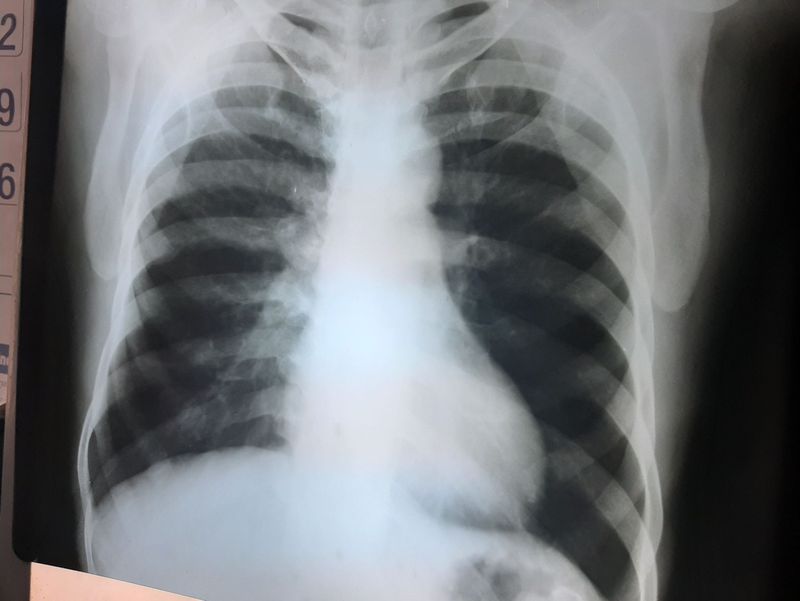

43 year old male having complaint of splitting blood since 2 days

Right hilar lesion , unilateral hilar lymphadenopathy ???!!